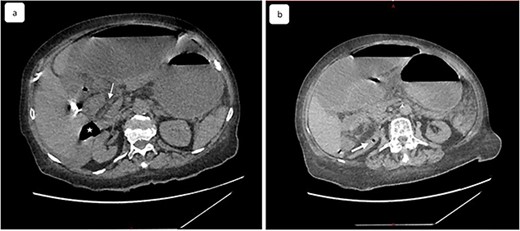

A 65-year-old woman presented to the emergency department with a complaint of acute abdominal pain and distention accompanied by nausea, vomiting and constipation of 2 days. She had a history of diabetes, hypothyroidism, dyslipidemia, mixed connective tissue disease and cholecystectomy. On examination, she had signs of septic shock with a hemodynamic instability, a Glasgow coma scale of 13 with generalized abdominal defense. Initial blood count showed elevated white blood cells (WBC) 22 000 elem/mm3 and C-reactive protein (CRP) of 500 mg/l and procalcitonin of 96 ng/ml. Her lactate on venous blood gas sampling doubled within an hour from 1.64 to 2.3 mmol/l. An urgent abdominal computed tomography (CT) was performed and revealed a dilated loop of bowel within the left upper quadrant and the lesser sac through the foramen of Winslow (Fig. 1). Furthermore, peritoneal fluid and some air bubbles related to intestinal perforation were observed in the omental bursa (Fig. 2). There was also mass effect on the hepatic hilum anteriorly and the inferior vena cava posteriorly. The stomach was pushed back antero-laterally with stretched mesenteric vessels directed to a central point (Fig. 3).

Multiple planes of computed tomography depicting the herniated cecum within the lesser sac. Reconstructed images: (A) axial, (B) and (C) sagittal views.